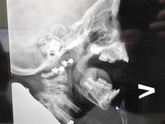

Дочь начала храпеть, пошли к Лору, она отправила на снимок. В итоге 3 степень (((но у нас подозрение на аллергический АД, а она сказала аллергики лучше поддаються лечению, поэтому на месяц выписала назонекс, если не станет лучше, то только удаление … Читать далее